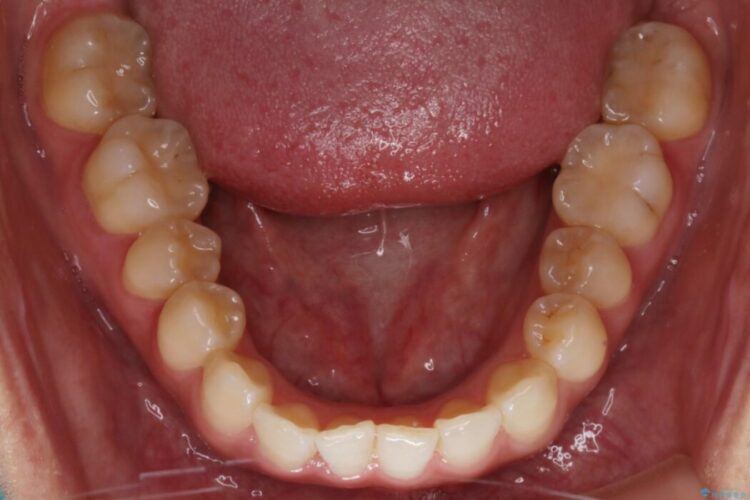

上顎歯列のガタガタを改善したいとのことで来院されました。

前歯の一部に反対咬合が見られ歯列がガタガタしていたためインビザラインでの矯正治療をご提案しました。

今回のケースでは前歯部の軽い凹凸のみであったため部分矯正の適応範囲に該当していました。